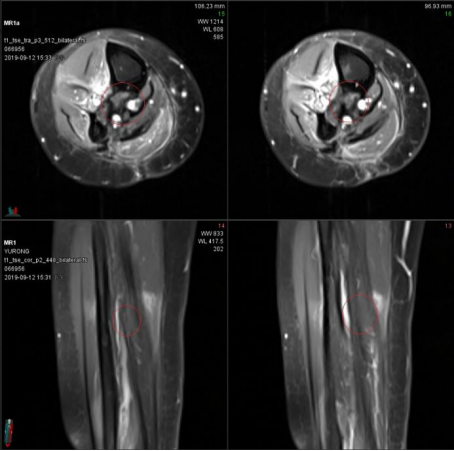

病例二:患者,女,55岁。病史:右小腿脂肪肉瘤,曾于2014年11月17日和2016年3月30日接受两次广泛切除术。第二次术后于2016年5月接受辅助放疗(总剂量50.4Gy/28次,后续加量10Gy/5次)。2018年11月1日,PET-CT和MRI(图1)显示肿瘤复发,病灶位于右胫腓骨中间隙,大小约4.2×2.0 cm。临床诊断为右小腿脂肪肉瘤复发。2018年11月,患者接受重(碳)离子治疗,治疗方案为:总剂量64Gy(RBE),分16次,在28天内完成(每周一至周五,每日一次),照射野设计采用两野计划(水平野和垂直野,见图2)。

图1. 治疗前影像学检查

(A) PET/CT轴位图像:可见高SUV摄取灶。(B) PET/CT矢状位图像:T2WI呈高信号。(C) MRI轴位和 (D) MRI矢状位图像。